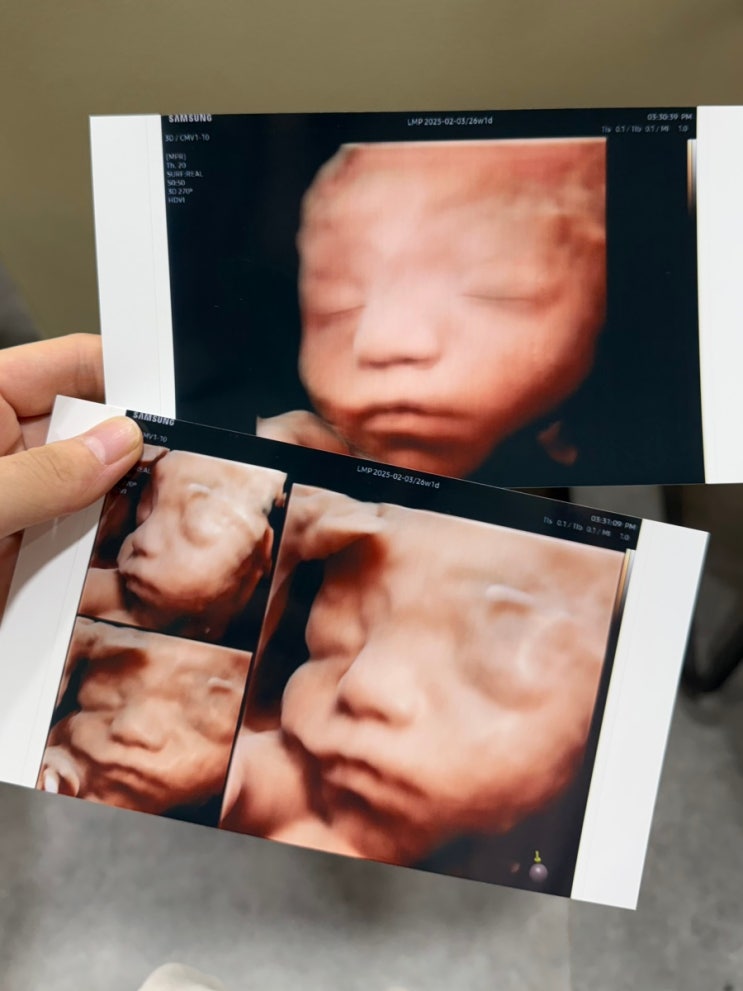

포유문 산부인과 입체초음파 가격 후기, 임당 검사

26주에 진행하는 임신성 당뇨 검사! 포유문 산부인과는 임신성 당뇨 검사 날에 입체초음파도 함께 볼 수 있...